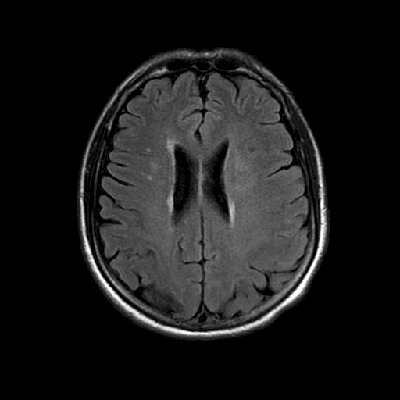

Neurologic and mental examination showed intact immediate memory but inability to recall 3 objects in 5 minutes. He was not oriented to time or space or situation but oriented to person. His remote memory was intact. There was left superior quadrantonopsia but no focal motor or sensory deficits. FLAIR images on MRI showed a lesion in the left mesial temporal lobe (Panel 1). This lesion had increased T2 signal but without enhancement on T1 images. This lesion also had mass-effect and edema within that region. On FLAIR images, there were some small foci of abnormal signal in the white matter of the right parietal lobe (Panel 2) but these foci did not enhance (Panel 3). There is a vague, poorly demarcated, triangular shaped periventricular signal abnormality in the left parietal lobe (Panel 2) but this area did not enhance (Panel 3). On another image (obtained higher to Panel 2 and 3), however, there is a small cluster of enhancing spotty signal in the white matter of the left parietal lobe (Panel 4) and the largest focus is about 0.4 cm in diameter. There were areas with features of encephalomalacia in his right mesial temporal lobe that would be explained by his history of prior infarct.

2. FLAIR |